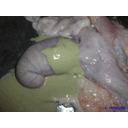

ovario histerectomie.jpg

ovario histerectomie[1].jpg